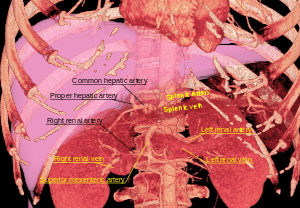

Blood supply

The renal circulation supplies the blood to the kidneys via the renal arteries, left and right, which branch directly from the abdominal aorta. Despite their relatively small size, the kidneys receive approximately 20% of the cardiac output.[7]

Each renal artery branches into segmental arteries, dividing further into interlobar arteries, which penetrate the renal capsule and extend through the renal columns between the renal pyramids. The interlobar arteries then supply blood to the arcuate arteries that run through the boundary of the cortex and the medulla. Each arcuate artery supplies several interlobular arteries that feed into the afferent arterioles that supply the glomeruli.

The renal artery enters into the kidney at the level of the first lumbar vertebra just below the superior mesenteric artery. As it enters the kidney, it divides into branches: first the segmental artery, which divides into 2 or 3 lobar arteries, then further divides into interlobar arteries, which further divide into the arcuate artery, which leads into the interlobular artery, which form afferent arterioles. The afferent arterioles form the glomerulus (network of capillaries enclosed in Bowman's capsule). From here, efferent arterioles leaves the glomerulus and divide into peritubular capillaries, which drain into the interlobular veins and then into arcuate vein and then into interlobar vein, which runs into lobar vein, which opens into the segmental vein and which drains into the renal vein, and then from it blood moves into the inferior vena cava.